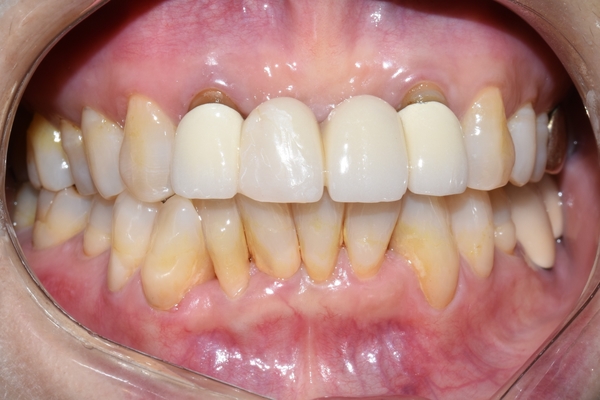

환자분이 너무 불투명하게 가짜같은 치아는 싫다고 하셔서

자연광에서, 입 안에서 보일 때 자연스러운 치아로 제작하였습니다.

그리고 당연히 누런 치아보다는 조금 더 밝은 치아가 나으므로 본인 치아와 잘 어우러지면서도

더 밝은 색상으로 디자인하였습니다.

위처럼 입안을 개구기로 훤히 들어냈을 때보다

입술로 그림자도 생기고 살짝 가려진 상태에서 더 자연스러워 집니다.

위 4개 치아가 브릿지 임에도 불구하고 지금 보이는 8개 치아 중

어떤 것이 브릿지인지 티나지 않습니다.

원래도 아름다우셨지만 깨끗하고 깔끔해진 앞니 덕에 더욱더 아름답고 고급스러운 이미지가

되셨습니다.

제작기간: 5일

동일한 위치에서 동일한 조건에서 찍은 사진입니다.

오래되고 깨진 PFM 브릿지 -> 새로운 PFM브릿지로 교체